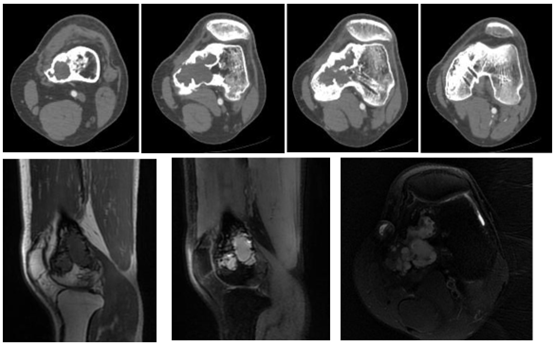

膝关节CT示:左股骨下段见不规则骨质破坏,大小约59*36mm,局部骨皮质增厚、局部骨皮质变薄欠连续,病灶局部见硬化边。

膝关节MRI示:左侧股骨下段及内侧髁见多斑片状不规则异常信号影,T1WI低,T2WI/PD,脂肪抑制高信号,边缘清晰,骨髓腔未见明显水肿改变。周围软组织未见肿胀。